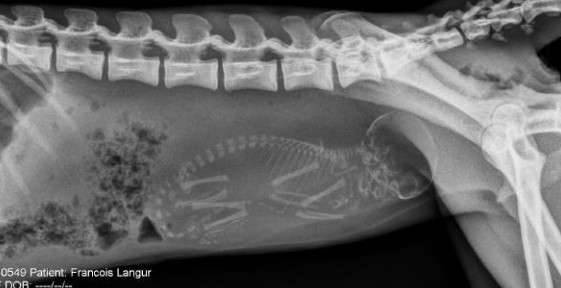

▼怀孕的猴子